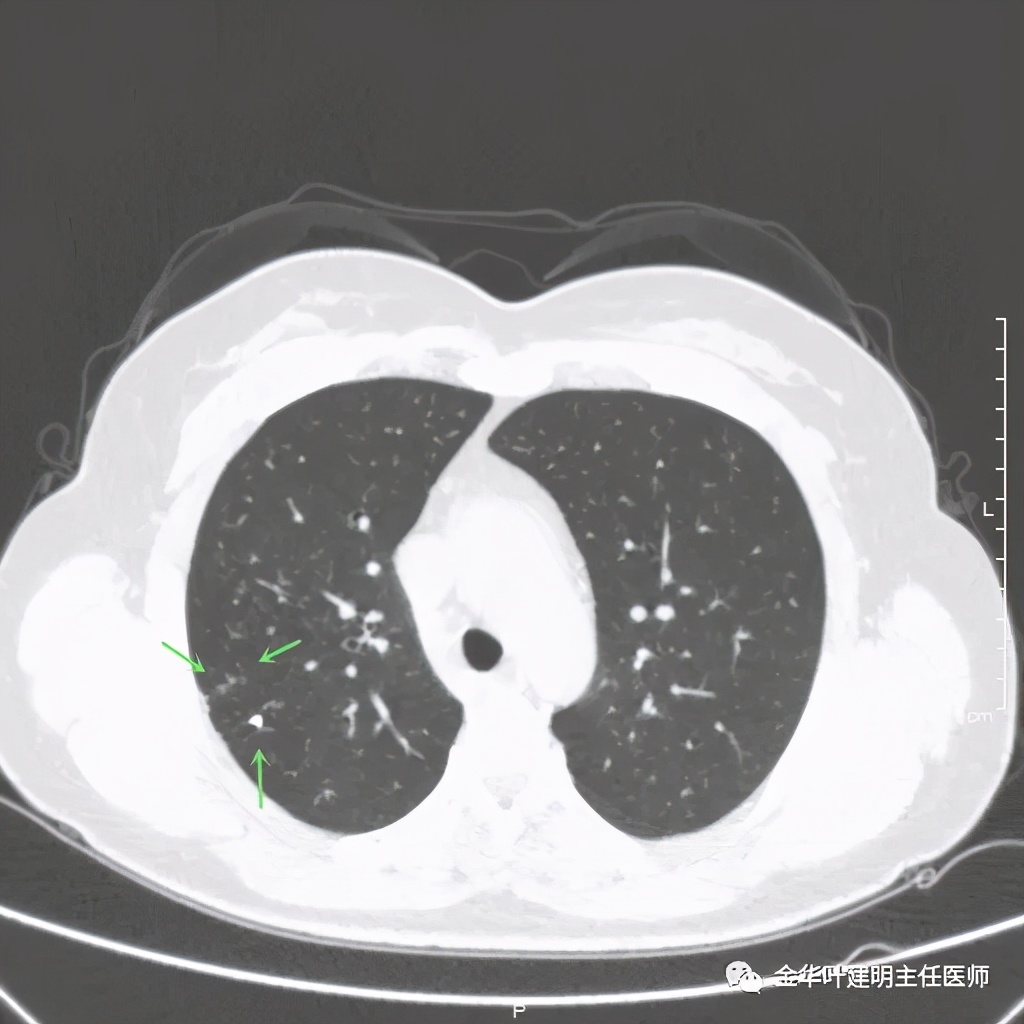

紫色箭头示病灶与胸膜很近,但无牵拉凹陷,绿色箭头示附近有微小其他病灶

主病灶非常光滑

上图同样示与胸膜近,但无牵拉

上图示病灶内侧有个小的空泡

距主病灶一段距离的地方,也有小的实性微结节

总体感觉病灶较大,但边缘过于光滑,缺乏收缩力,没有毛刺征、分叶征、胸膜凹陷征;旁边却有多发微小实性或似磨玻璃结节,周围不清爽。让人感觉非肿瘤性质,炎性可能性大些,比如结核等。那么纵隔窗又是如何呢?我们选两个层面来看: